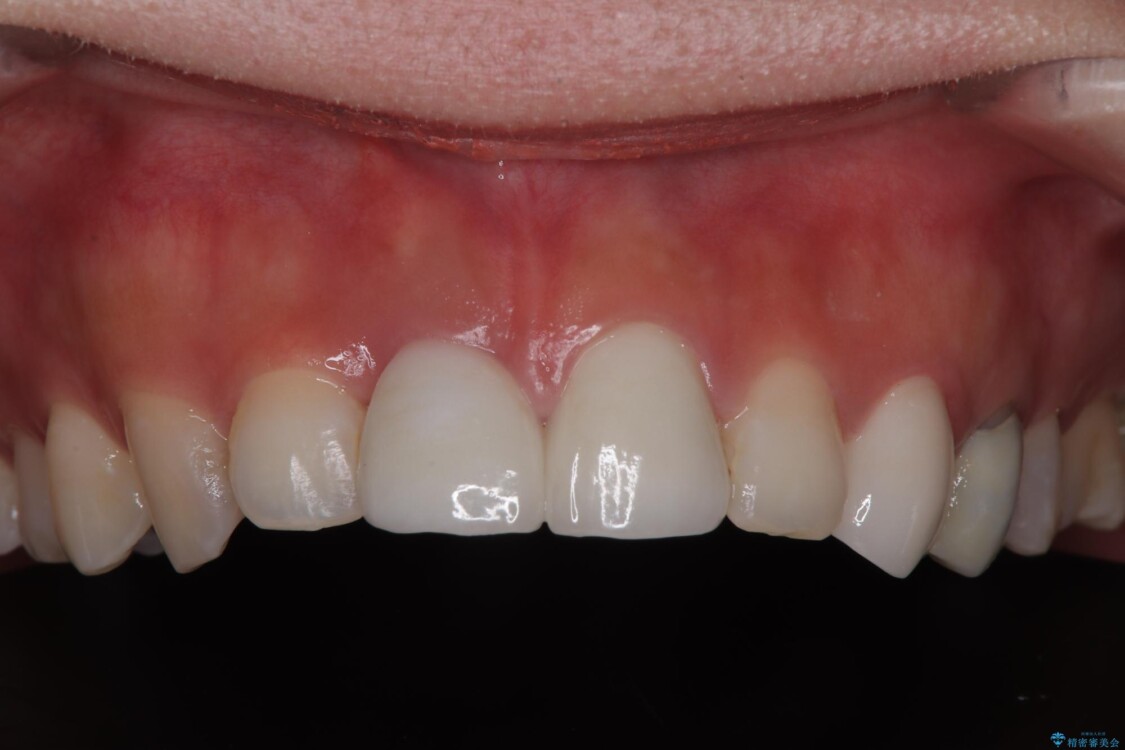

治療後

• 「抜歯してブリッジ」と言われた20代女性が選んだ治療とは|たった4か月で自然な笑顔に抜歯即時インプラント+審美補綴の症例 治療後画像

抜歯を避けられない場合でも、「即日でインプラント治療+仮歯装着」により見た目を損なわないで治療を終えることができました。

抜歯をしてインプラントを埋入してから、4か月で最終補綴物(オールセラミッククラウン)の装着まで終えることができ非常に満足いただきました。